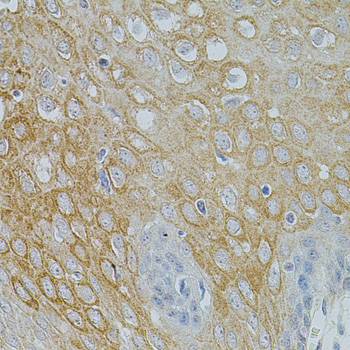

Immunohistochemistry of paraffin-embedded esophagus tissue(hu) using NTF3 antibody at dilution of 1:100 (x40 lens).